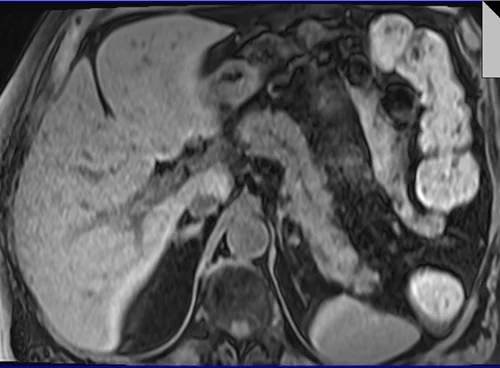

MRI PANCREAS TI VIBE PRE 2 - MRI